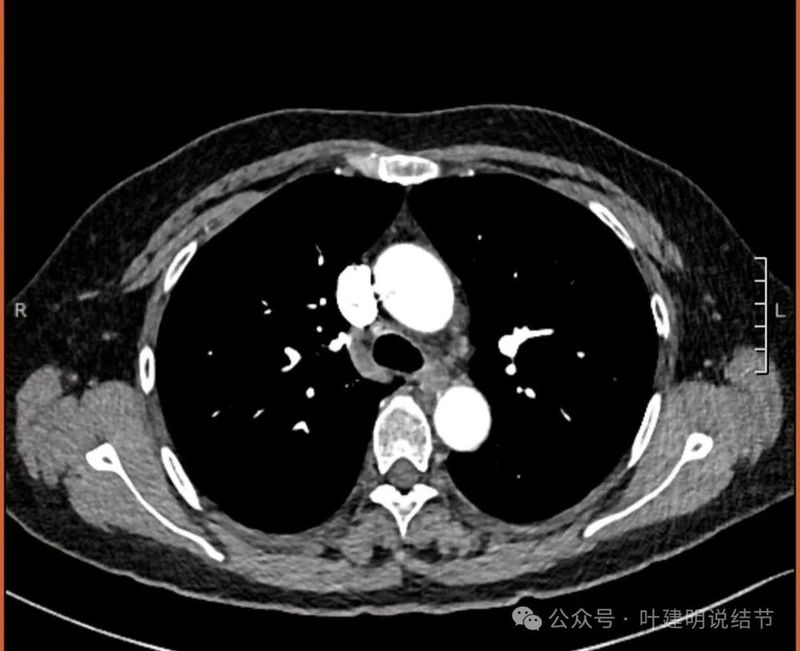

纵隔与肺门没有见到显著增大融合要考虑转移的淋巴结。